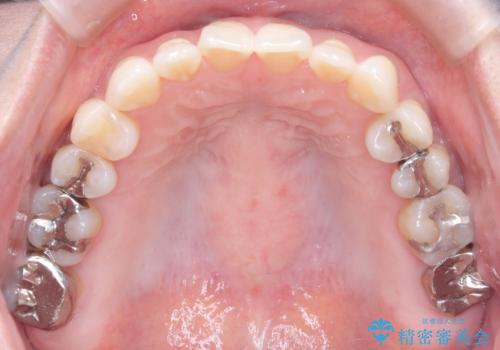

- 上の前歯の捻れと、前歯で物が噛めないことを主訴に来院されました。

前歯の翼状捻転とオープンバイト傾向だったため、インビザラインにて矯正を行いました。右下の奥歯は保存不可だったため、抜歯を行いインプラントにて修復を行なっています。

翼状捻転はインビザラインでは苦手とする動きですが、ここまで綺麗に治すことができました。